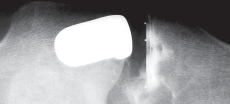

التصوير الطبي

التصوير الطبي ضروري لتأكيد التشخيص وتحديد مدى تلف المفصل:

-

الأشعة السينية العادية (Plain Radiographs):

- المنظر الأمامي الخلفي (AP): يُظهر الركبة من الأمام.

- المنظر الجانبي (Lateral): يُظهر الركبة من الجانب.

- المنظر الخلفي الأمامي المثني (PA Flexed): يسمح بتقييم أفضل للجزء الخلفي من الركبة وقد يكشف عن تغيرات أكبر في الحجرة الخلفية الوحشية.

- منظر شروق الشمس (Sunrise/Patellofemoral): لتقييم المفصل الرضفي الفخذي.

- الأشعة السينية الطويلة للطرف السفلي بالكامل (Full-length standing radiographs): من الورك إلى الكاحل، وهي مفيدة جدًا، خاصة إذا تم استخدام تقنيات الملاحة الحاسوبية. تُظهر هذه الأشعة المحاذاة الكلية للطرف السفلي.